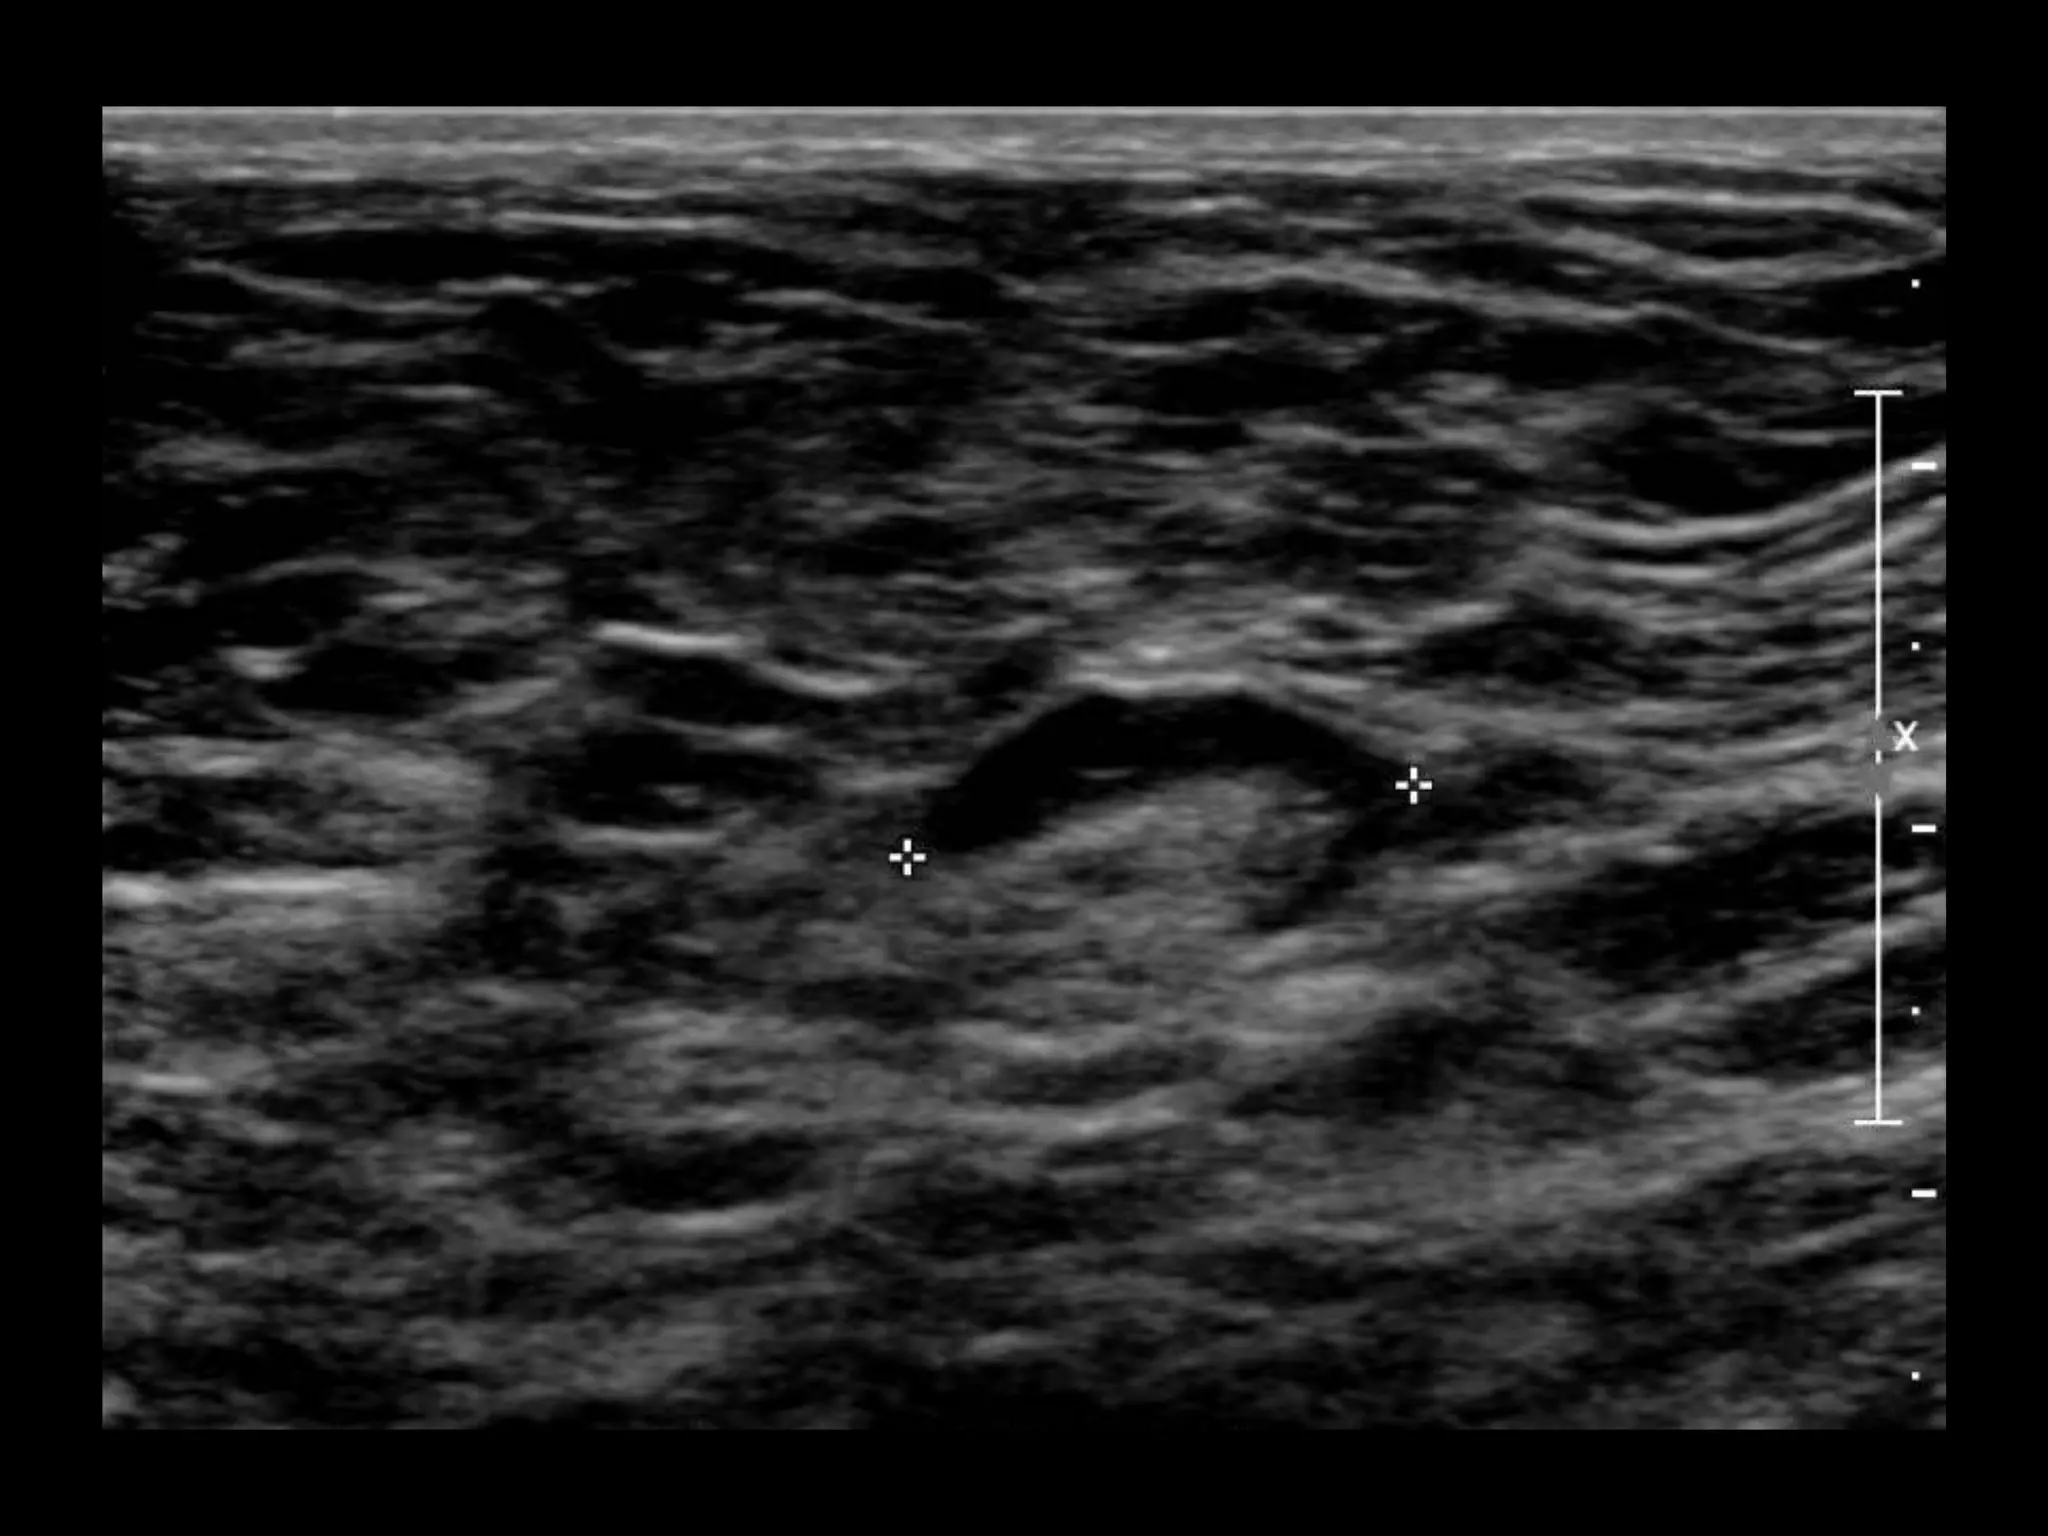

US retroareolar region

US Left upper outer breast

US retroareolar region US Left upper outer breast